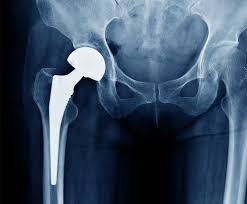

Hip joint issues, including arthritis, fractures, and degeneration, can significantly reduce mobility and overall quality of life. Therefore, accessing precise and advanced surgical care is crucial. At Varunam Hospital, Sagar, patients receive precision hip replacement under the expert guidance of Dr. Utsav Agrawal, which combines meticulous surgical planning, advanced technology, and personalized care. Precision techniques ensure accurate implant placement, minimize tissue damage, and provide optimal joint function. Consequently, patients experience faster recovery, reduced pain, and improved long-term mobility, allowing them to resume daily activities confidently.

Precision Hip Replacement In Sagar

At Varunam Hospital, Sagar, Dr. Utsav Agrawal leads the precision hip replacement program with extensive experience and advanced skills. He begins by performing a detailed evaluation, including imaging studies, joint assessment, and reviewing the patient’s medical history. Then, he develops a personalized surgical plan tailored to the patient’s anatomy and lifestyle needs. Using advanced instruments and precision techniques, he performs the surgery to ensure proper alignment, stability, and long-term function of the hip joint. Moreover, patients are guided throughout every stage, from preoperative preparation to postoperative rehabilitation, ensuring clarity, confidence, and comfort.

During precision hip replacement, surgeons focus on exact implant positioning to achieve balanced joint movement. Modern surgical techniques help preserve surrounding muscles and tissues. Consequently, patients experience less pain and faster recovery. Accurate execution reduces the risk of implant loosening and uneven wear. This precision supports better mobility and long-term durability of the hip joint.

Varunam Hospital, Sagar is equipped with modern operation theaters, advanced monitoring systems, and precise surgical instruments. These facilities allow Dr. Utsav Agrawal to perform precision hip replacements safely and efficiently. The hospital maintains strict hygiene standards, emergency support, and intensive care units to ensure patient safety at all times. By combining surgical expertise with advanced technology, patients benefit from reliable, effective, and long-lasting results.